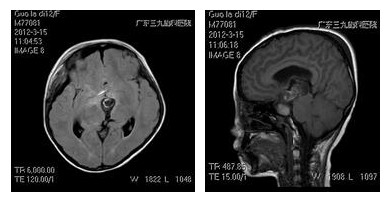

入院后,小儿神经外科的专家团队在全麻下为其行“右侧翼点入路颅咽管瘤切除术”,显微镜下将肿瘤次全切除。术后2小时,患儿完全苏醒,对答切题,复查头部磁共振:显示肿瘤近全切除,脑积水解除。出院时,患儿一般状况好,神清语利,右眼视力0.1,左眼视力0.8,肢体肌力5级。

术后